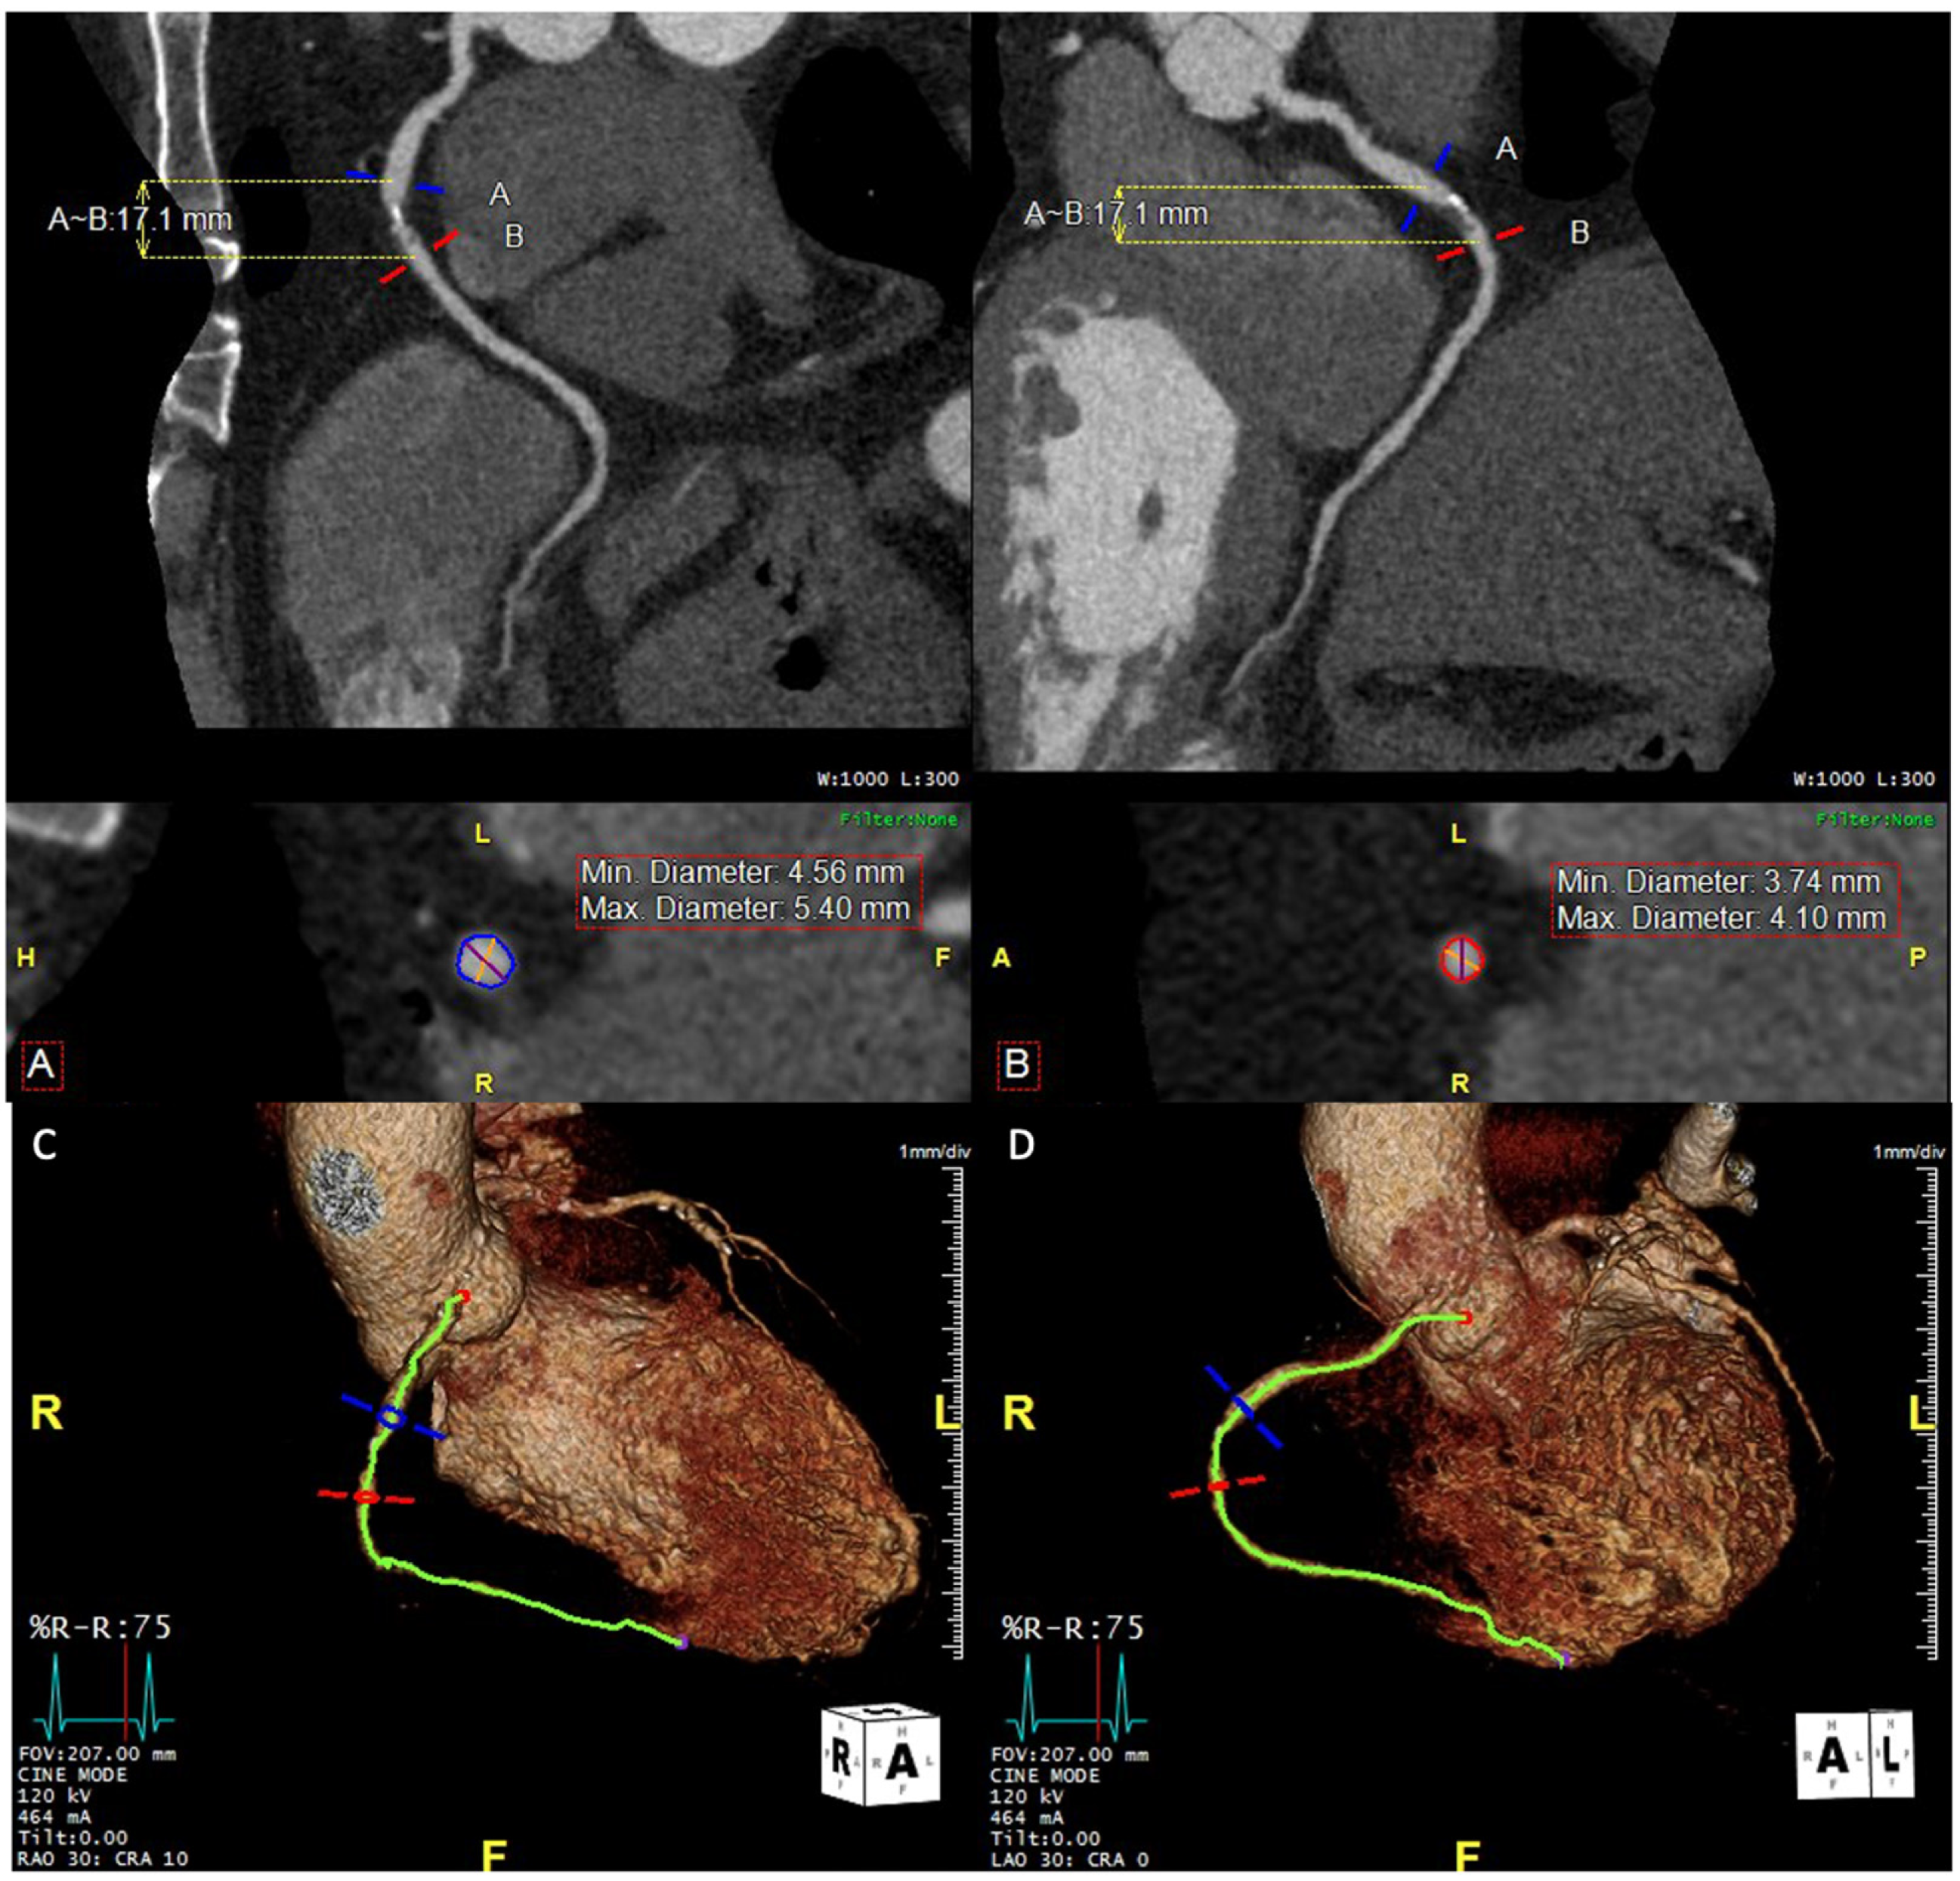

2. Anatomical Evaluation of Coronary Arteries

7.5. Chronic Total Occlusion (CTO)